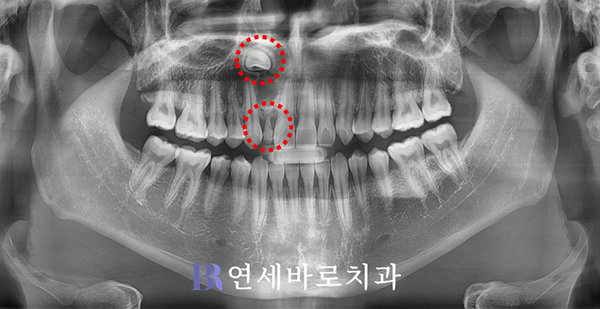

엑스레이를 촬영해보았습니다.

방사선 사진으로 보니 앞니가

정상적인 영구치가 아니라

제때 탈락하지 못한 유치임을

확인해볼 수가 있었습니다.

진짜 치아는 잇몸의 깊은 곳에

묻혀있다는 점이 드러났지요.